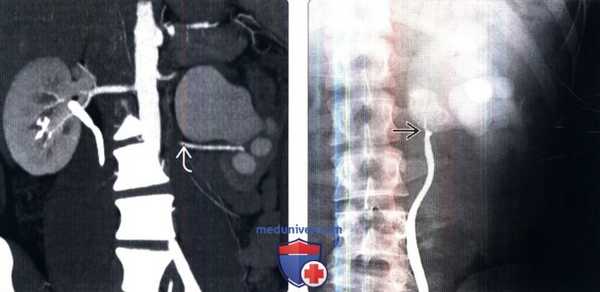

(Слева) КТ с контрастированием, аксиальная проекция: расширенные почечные чашечки и лоханки с наличием мочеточникового стента. В этой плоскости визуализировано взаимоотношение расширенной почечной лоханки с ветвью почечной артерии.

(Справа) При объемной 3D КТ у этого пациента визуализировано пространственное взаимоотношение между почечными артериями и почечной лоханкой. Этот снимок важен при оценке пациентов для возможной эндоуретральной операции, которая может быть противопоказана, если пиелоуретеральный сегмент прилегает к артериальным ветвям.

(Слева) КТ с контрастированием, аксиальная проекция: гидронефроз левой почки, замедленная нефрограмма и легкое истончение коркового вещества. Левый мочеточник нормальный, отсутствуют какие-либо внутренние или наружные объемные образования, а также процессы, вызывающие обструкцию. Взаимоотношение между структурами почечных ворот не отображено в оптимальном виде.

(Справа) КТ с контрастированием, коронарный срез, проекция максимальной интенсивности: у этого пациента визуализированы левая сторона гидронефроза и ветвь почечной артерии верхнего полюса.